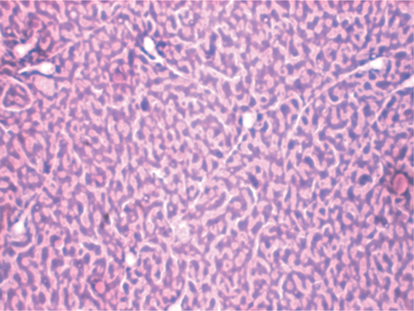

What does a normal spermatozoa head look like?

oval head